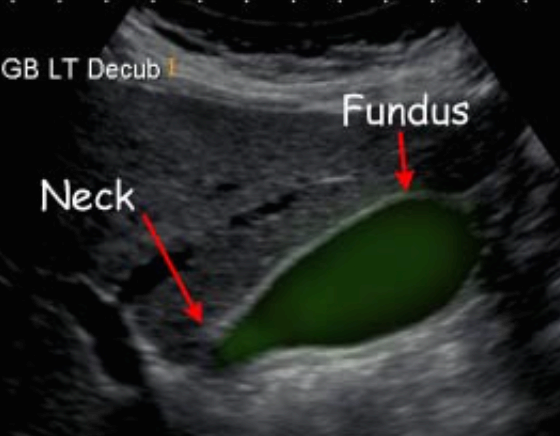

담낭 해부학 (GB anatomy ) 담낭은 길이는 7~10cm, 폭 3~5cm으로 간과 함께 복막에 싸여 있으며 간우측하면 담낭와에 고정되어 있다. 담낭은 저부(fundus), 체부(body), 경부(neck)로 구분된다. 담낭의 저부는 복측에 있고 경부는 배 측에 있다. 담낭의 저부는 담낭암의 호발부위이고 담낭의 체부는 저부와 경부 사이에 있으며 경부는 담낭관으로 연결되는 부분으로 누두부(hartman pouch)가 있다. 담낭관(cystic duct)은 약 2~4cm이고 내강에 heister valve 가 있어 담즙의 역류를 방지한다. 담낭벽은 매우 얇은 벽을 갖는 주머니로 점막층, 점막하층, 근육층, 장막층으로 구성되며 식전에는 2mm 이하 식후에는 3mm 이하의 두께를 갖는다.

간의 주엽열(main lobe fissure)은 고에코의 선으로 보이고 초음파에서 담낭을 찾는 지표이다. 담낭과 하대정맥(IVC)이 일치하는 선상을 Cantle's line이라고 한다.